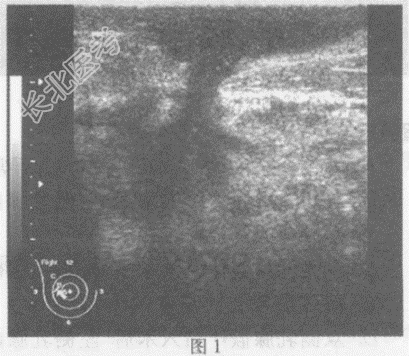

超声综合描述: 右乳腺腺体层厚度2.8cm,明显增厚, 结构紊乱,内回声明显不均, 乳头外侧及外下象限可见数个大小不等,形态不规则极低近似无回声区(图1、图2、图3), 部分呈树枝状分布,探头加压后局部压痛明显; 右乳头外上象限可见形态不规则片状低回声(图4),CDFI: 右乳腺腺体层内血流信号较左侧丰富。